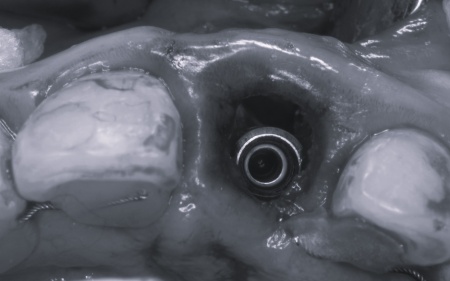

まずは左上前歯にエクストリュージョンを行い、歯と歯茎の境目を整えたうえで抜歯を行います。抜歯と同時にインプラントを埋め込み、治療中の審美性を考慮して仮歯を装着しました。

その後、インプラントと骨がしっかりと結合するまで、経過観察を行います。

後日、インプラントと骨が結合したことが確認できたら、インプラントに装着する最終的な被せ物を作製するため、精密な型取りを行います。